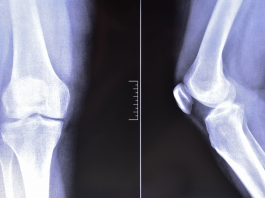

Artrosi del ginocchio: la fisioterapia digitale migliora dolore e funzione

Le tecnologie digitali stanno assumendo un ruolo crescente nella riabilitazione dei pazienti con patologie muscoloscheletriche. Una nuova revisione...